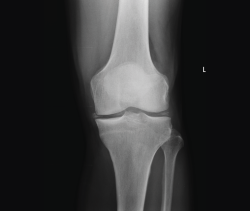

La radiología es útil para el diagnóstico de las fracturas, luxaciones, osteoartritis o para cuantificar las desviaciones axiales y planificar las cirugías de realineación(1).

Es el procedimiento de imagen empleado generalmente como primera elección y es muy útil para la visualización de los elementos óseos, con la limitación que supone la superposición en un mismo plano de todas las estructuras atravesadas por los rayos X.

Deben hacerse proyecciones anteroposterior (AP) y lateral, generalmente con flexión de 30°, y axial de la rótula cuando se sospeche patología de esta; y proyecciones especiales oblicuas o laterales, proyecciones forzadas de varo o valgo, y AP en 45°, para valorar mejor la interlínea articular(2).

1.1.1. Fémur (Figura 1)

Figura 1. Radiografías anteroposterior y lateral de rodilla: fractura longitudinal del fémur extendida a la articulación.